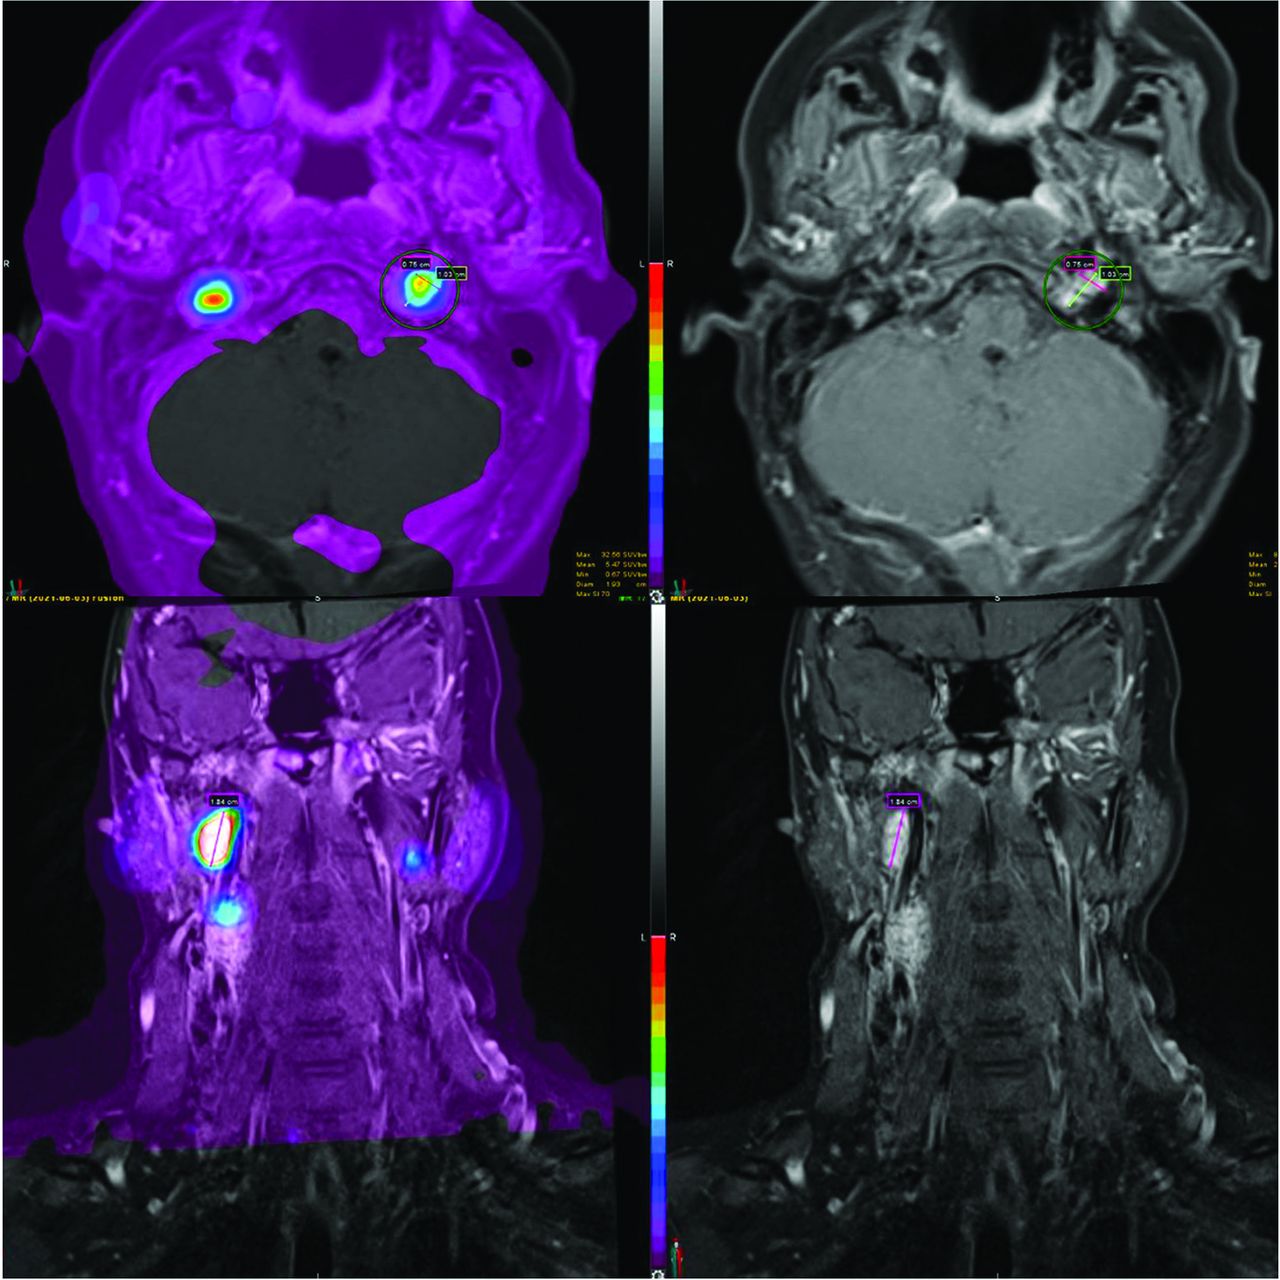

A 31-year-old woman with a vividly enhancing submandibular mass positive for neuroendocrine markers. The patient had SSTR-avid carotid body tumors, a glomus vagale tumor, and glomus jugulare tumors bilaterally. In this example, SSTR-PET/MRI findings were more extensive than on the basis of structural imaging because the right glomus jugulare tumor was not identified on contrast-enhanced MR imaging.